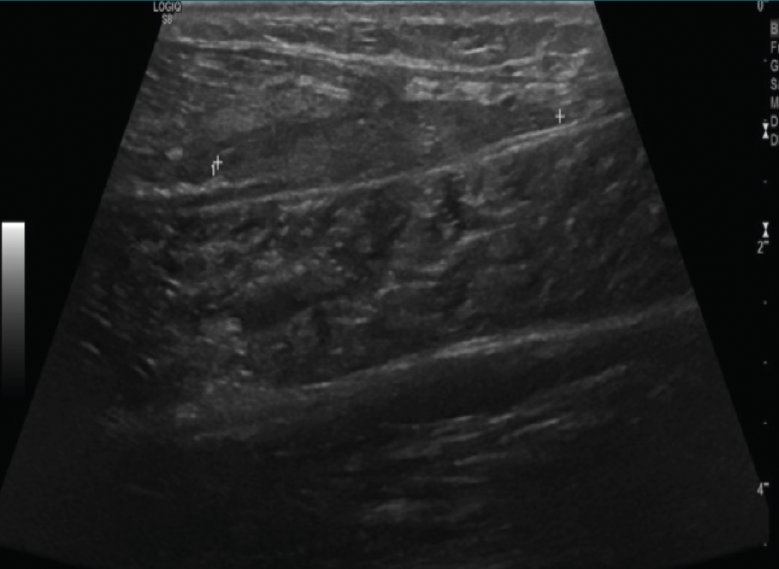

Se observa una colección hipo- o anecoica con refuerzo acústico en lesiones líquidas y sin refuerzo acústico en lesiones sólidas. También puede ser hiperecoica en casos de contenido graso (Figuras 15, 16 y 17).

Figura 15. Corte axial con sonda lineal del tercio proximal de la pierna: gran colección flemonosa intramuscular del gemelo.

4. Bultomas